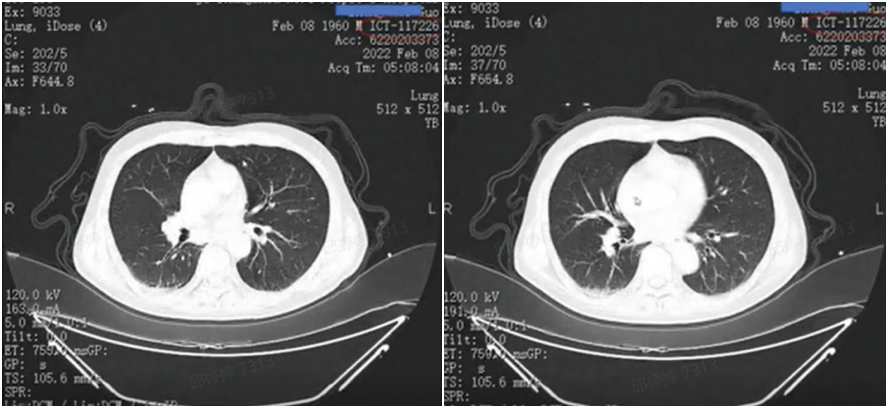

2022年2月8日复查CT提示,肺部病灶基本消失(图11),肾上腺病灶明显缩小,髂骨病灶进一步退缩(图12)。2022年2月9日AFP为411ng/ml。

图11.2022年2月8日复查胸部CT